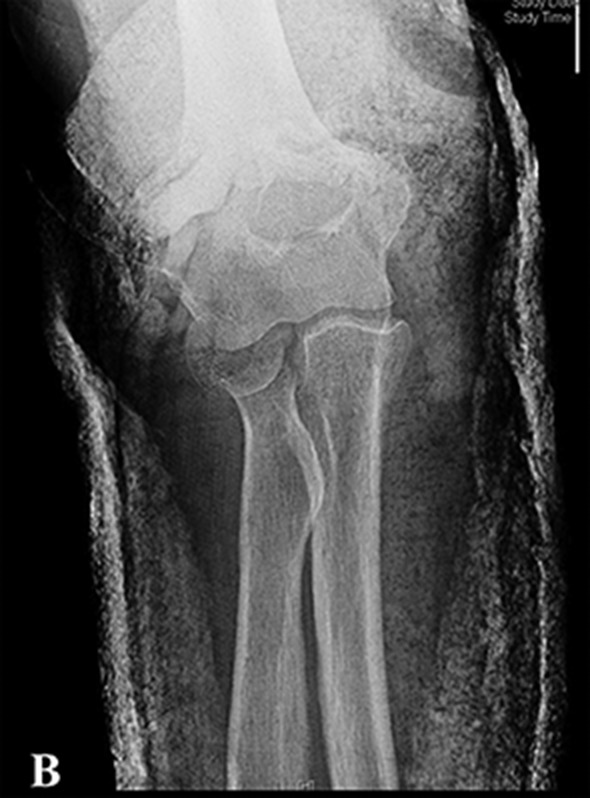

Figs 1-A through 1-H Preoperative and postoperative imaging of a patient who underwent a radial head replacement following radial head fracture.

Fig. 1-B.

Figs. 1-A and 1-B Lateral (Fig. 1-A) and anteroposterior (Fig. 1-B) radiographs typically provide sufficient information for the diagnosis and treatment of radial head fractures.